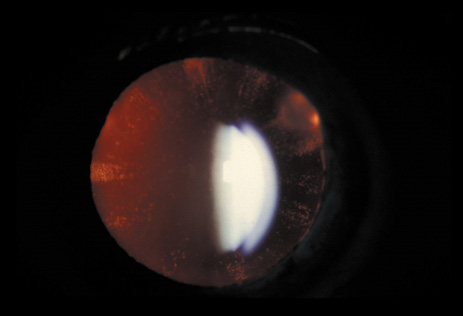

Anterior lenticonus (Figs. 8 and 9) is considered an integral part of AS. The anterior capsule thins and allows the lens to bulge into the anterior chamber, using the pupil as a mold.53 Electron microscopy of the renal glomeruli and anterior lens capsule can confirm capsular thinning and dehiscences.54,55 Anterior lenticonus is typically diagnosed in the second and third decades of life, when it causes clinically significant decreased vision,56 but it may be present in adolescence and result in spontaneous rupture of the anterior lens capsule.57 Posterior subcapsular cataract occurs quite frequently; however, many patients receive glucocorticosteroids for their renal condition, which may play an etiologic role in these cataracts. Additional ocular features described in XLAS include other corneal dystrophies, microcornea, corneal arcus, iris atrophy, posterior lenticonus, spontaneous lens rupture, spherophakia, a poor macular reflex, fluorescein angiogram hyperfluorescence, electrooculogram and ERG abnormalities, and retinal pigmentation abnormalities.58

Fig. 9. AS. Oil-droplet appearance of anterior lenticonus in retroillumination. (Courtesy of Dr. N. Meadow, Manhattan Eye and Ear Hospital, New York, New York.)